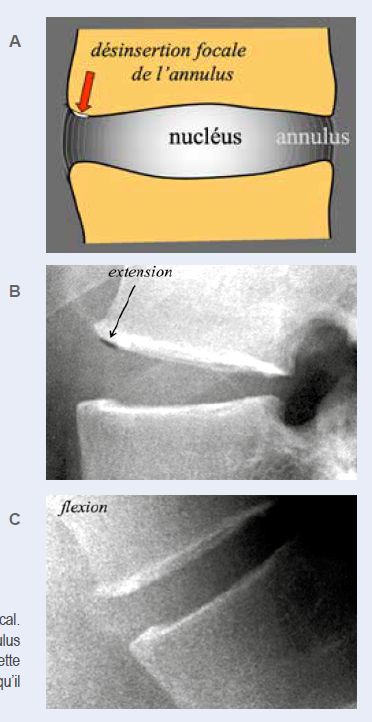

B. ANNEAU FIBREUX DISCAL

Un second site fréquent de phénomènes du vide est situé dans des interruptions de fibres de l’anneau fibreux au niveau de leur insertion sur le plateau vertébral (fibres de Sharpey), très souvent même en l’absence de pathologie du nucléus pulposus. Les phénomènes du vide dans ce territoire ont l’aspect de fines collections gazeuses linéaires accolées au plateau vertébral à proximité de sa marge antérieure et apparaissent plus fréquemment sur des clichés en extension (Figure 7).

![]() |